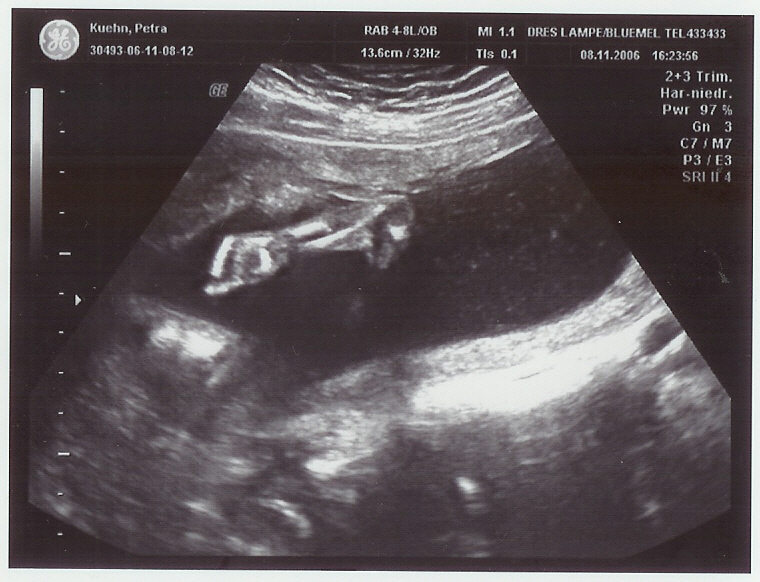

wir kommen gerade von der Feindiagnostik.

Leider hat es auch heute noch kein Outing gegeben.

Aber dafür sind alle sichtbaren Organe in Ordnung

und die Durchblutung ist super.

Es gab auch keine spektakulären Bilder,

aber ein Süßes habe ich angehängt.

Da hat das Würmchen uns voll zugewinkt.

auf dem Bild ist das Baby nicht zu sehen,

sondern nur der Arm.

Die Ärztin fand das so witzig,

weil das Kleine die Hand immer auf und zu gemacht hat.